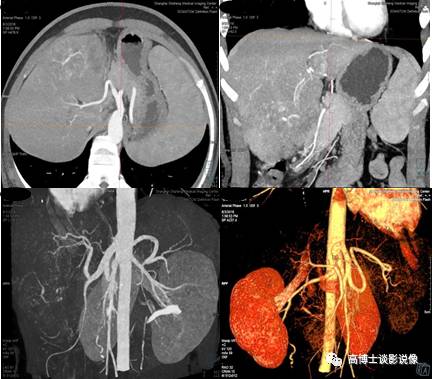

五、肝脏肿瘤血管CTA术前评估

动脉期进行MIP重建,显示肝脏肿瘤的供血动脉特点、供血类型,显示有无动静脉瘘形成。采用去骨的VR图像,显示肝动脉及肠系膜上动脉的整体解剖形态,显示有无解剖变异及其类型。

六、肾肿瘤血管术前评估

MIP重建显示肾脏肿瘤的供血类型、供血动脉、肿瘤血管团及有无动静脉瘘形成,显示动脉血管有无侵犯,显示肾静脉、下腔静脉内有无癌栓形成。去骨VR整体、直观显示双肾动脉整体解剖和变异血管起源、数目、走行等,判断其变异类型,显示有无异常血管团及狭窄、中断。为外科手术方案的制订、预防术中并发症及预测肿瘤的可切除率方面提供依据。